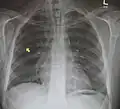

Neumomediastino y neumotórax derecho tras fractura de la primera costilla en accidente de bicicleta de montaña. -

Neumomediastino con el signo del ala de ángel.[18] -